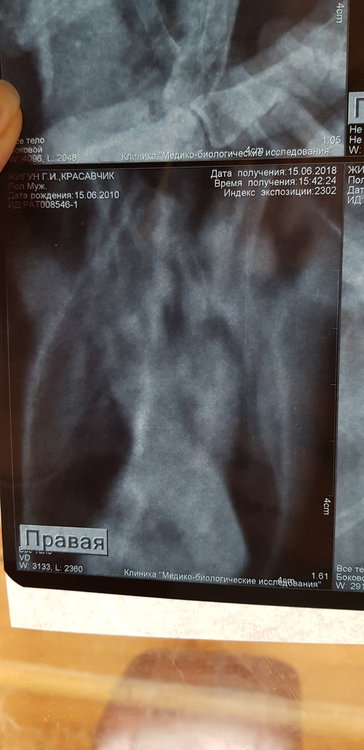

Сделала рентген. Но я в нем не разбираюсь.  Есть ли там грибы в легких. 3 дня по чуть-чуть совсем так чтобы выходило примерно 5 по на день орунгамин. И сейчас ему совсем плохо. Один глаз закрыт, помутнеет. Постоянно пытается отрыгнуть или делает такие движения. Совсем вялый. Фото прикреплю в сообщении ниже